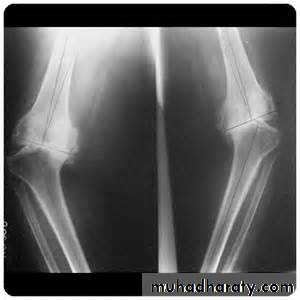

Plain X-ray of the affected joint (diagnostic features, severity of structural damage)Non-weight bearing postero-anterior views of the pelvis are adequate for assessing hip OA.

Patients with suspected knee OA should have standing antero-posterior radiographs taken to assess tibio-femoral cartilage loss, and a flexed skyline view to assess patello-femoral involvement.

Varus (less commonly valgus) deformity &/or fixed flexion deformity

Restricted flexion/extension with coarse crepitusBony swelling around the joint line

Varus deformity of the knee